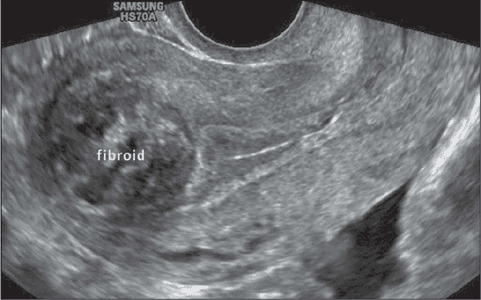

The four main type of the uterine fibroid are intramural, submucosal, subserosal and pedunculated fibroid. each are different from other based on location in uterus.

Intramural Fibroids: take origin within the uterus wall, it is the most common type of uterine fibroid, can enlarge and distort the uterus. cause heavy bleeding, pain and weighted feeling the pelvic region.